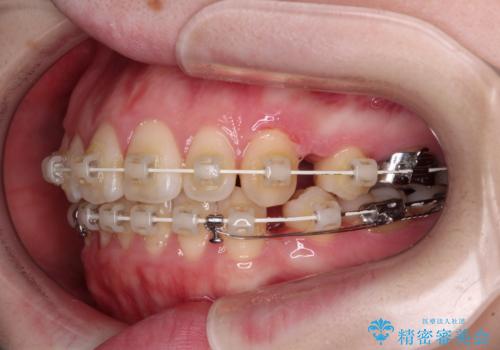

- 審美装置

- 2年9ヶ月

- 30回以上

上顎前歯をしっかりと後方に移動させるため、口蓋側にアンカースクリューと補助装置を併用し、上下左右の第一小臼歯4本を抜歯し、ワイヤー装置にて矯正治療を行うこととしました。

また、舌のトレーニングをしっかりと行うことで、突出癖改善を試みることとしました。